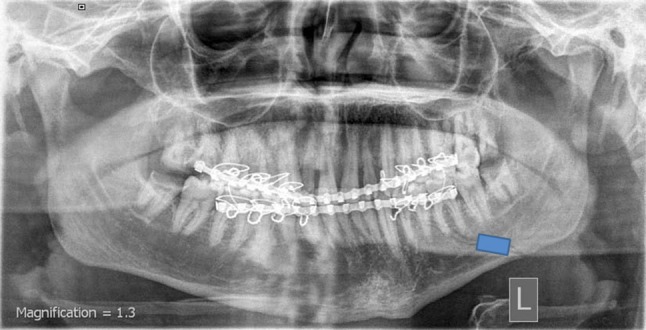

The digital images were manipulated using the IDRISI software (IDRISI is a raster-based image processing program inspired by Clark Labs, Clark University, USA). On each image, an analysis of the changes in the mean gray value was performed using the polygon measurement facility of the used software. The unit of measurement for bone density is pixels (mean gray value). A rectangular area of 10 × 15 mm was drawn along the center of the fracture line. The obtained densitometry values were expressed in gray levels from 0 to 256. Each of these values corresponded to the mean density of the fracture area (Fig. 1). In an attempt to eliminate intra-observer error, these measurements were performed twice by the same investigator who was unaware of the randomization codes. The data of the 2 trials were pooled, and the mean was included in additional statistical analysis. All collected data were then tabulated and statistically analyzed.

Fig. 1.

Processing of the digitized image along a rectangular area of 10 × 15 mm centered on the fracture line

The postoperative radiographs of all patients revealed good bony alignment of the bony segments (Fig. 1). Table 2 summarizes the assessment of the changes percentages of the bone density values in each group throughout the study period. In all groups, comparison between the study intervals with respect to both means and changes percentages of the bone density values showed insignificant differences. However, the changes in bone density within the same period were dependent on the treatment modality used (Fig. 2). This became obvious after the expression of the increase or decrease in the bone densities in percentages. At 2nd postoperative week, the mean bone density at the fracture sites decreased by 4.74, 6.6 and 27.89 % in groups A, B and C respectively. The period from the 2nd to the 4th postoperative weeks showed increase in the bone density by 1.49, 1.95 and 14.12 % in groups A, B and C respectively. The decrease percentages in the mean density at the 4th postoperative week in comparison to the baseline were 3.32, 4.78 and 17.71 in groups A, B and C respectively.